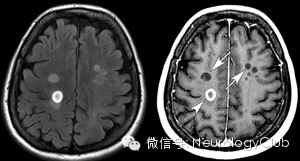

第三方面:胼胝体病变

1T2矢状位观察

2、特征:病灶以带毛缘的形态自胼胝体向外延伸,“虫蚀样”或称道森指征(Dawson’s finger sign)

3、可与脑血管病等鉴别